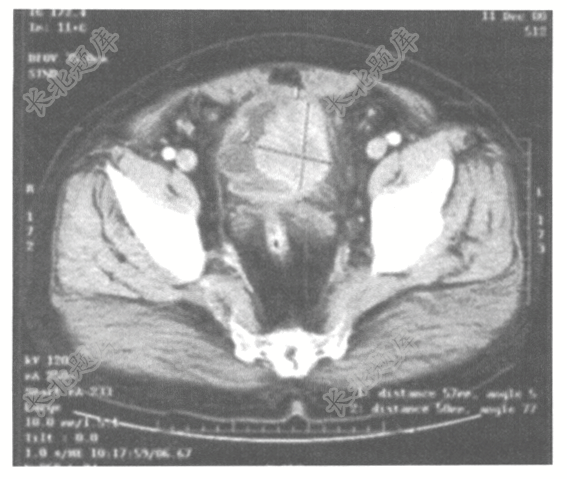

- 单项选择题男性,55岁,无痛性血尿3天,CT检查如下图,诊断结果为( )

A、肾癌

B、前列腺癌

C、膀胱癌

D、精囊腺癌

E、输尿管癌